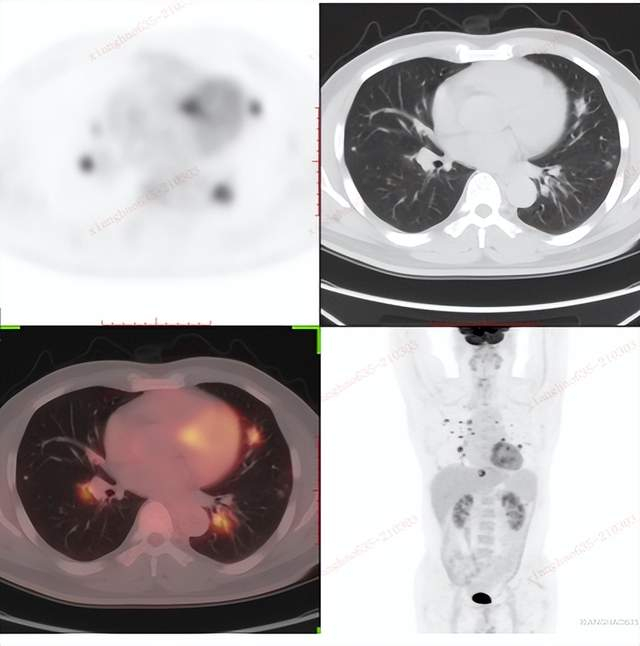

CT肺部扫图像

双肺散在多发结节,部分结节内见空洞形成。

PET/CT影像学表现

肺部结节广泛摄取,且左肾上极疑似环形代谢增高,与尿液摄取重叠,影像诊断。

大量饮水、排尿,反复多次,两小时后再次扫描:

PET/CT结论:

左肾上极环形代谢增高影,CT未见异常密度,考虑肾癌,建议临床进一步检查。双肺多发类圆形结节、结片影,部分含空洞,代谢不同程度增高,考虑转移瘤。

肺部结节穿刺病理结果:

肺低分化肉瘤样癌,肾来源性。

对比结论:

PET-CT实现肿瘤的精准定位及确诊。